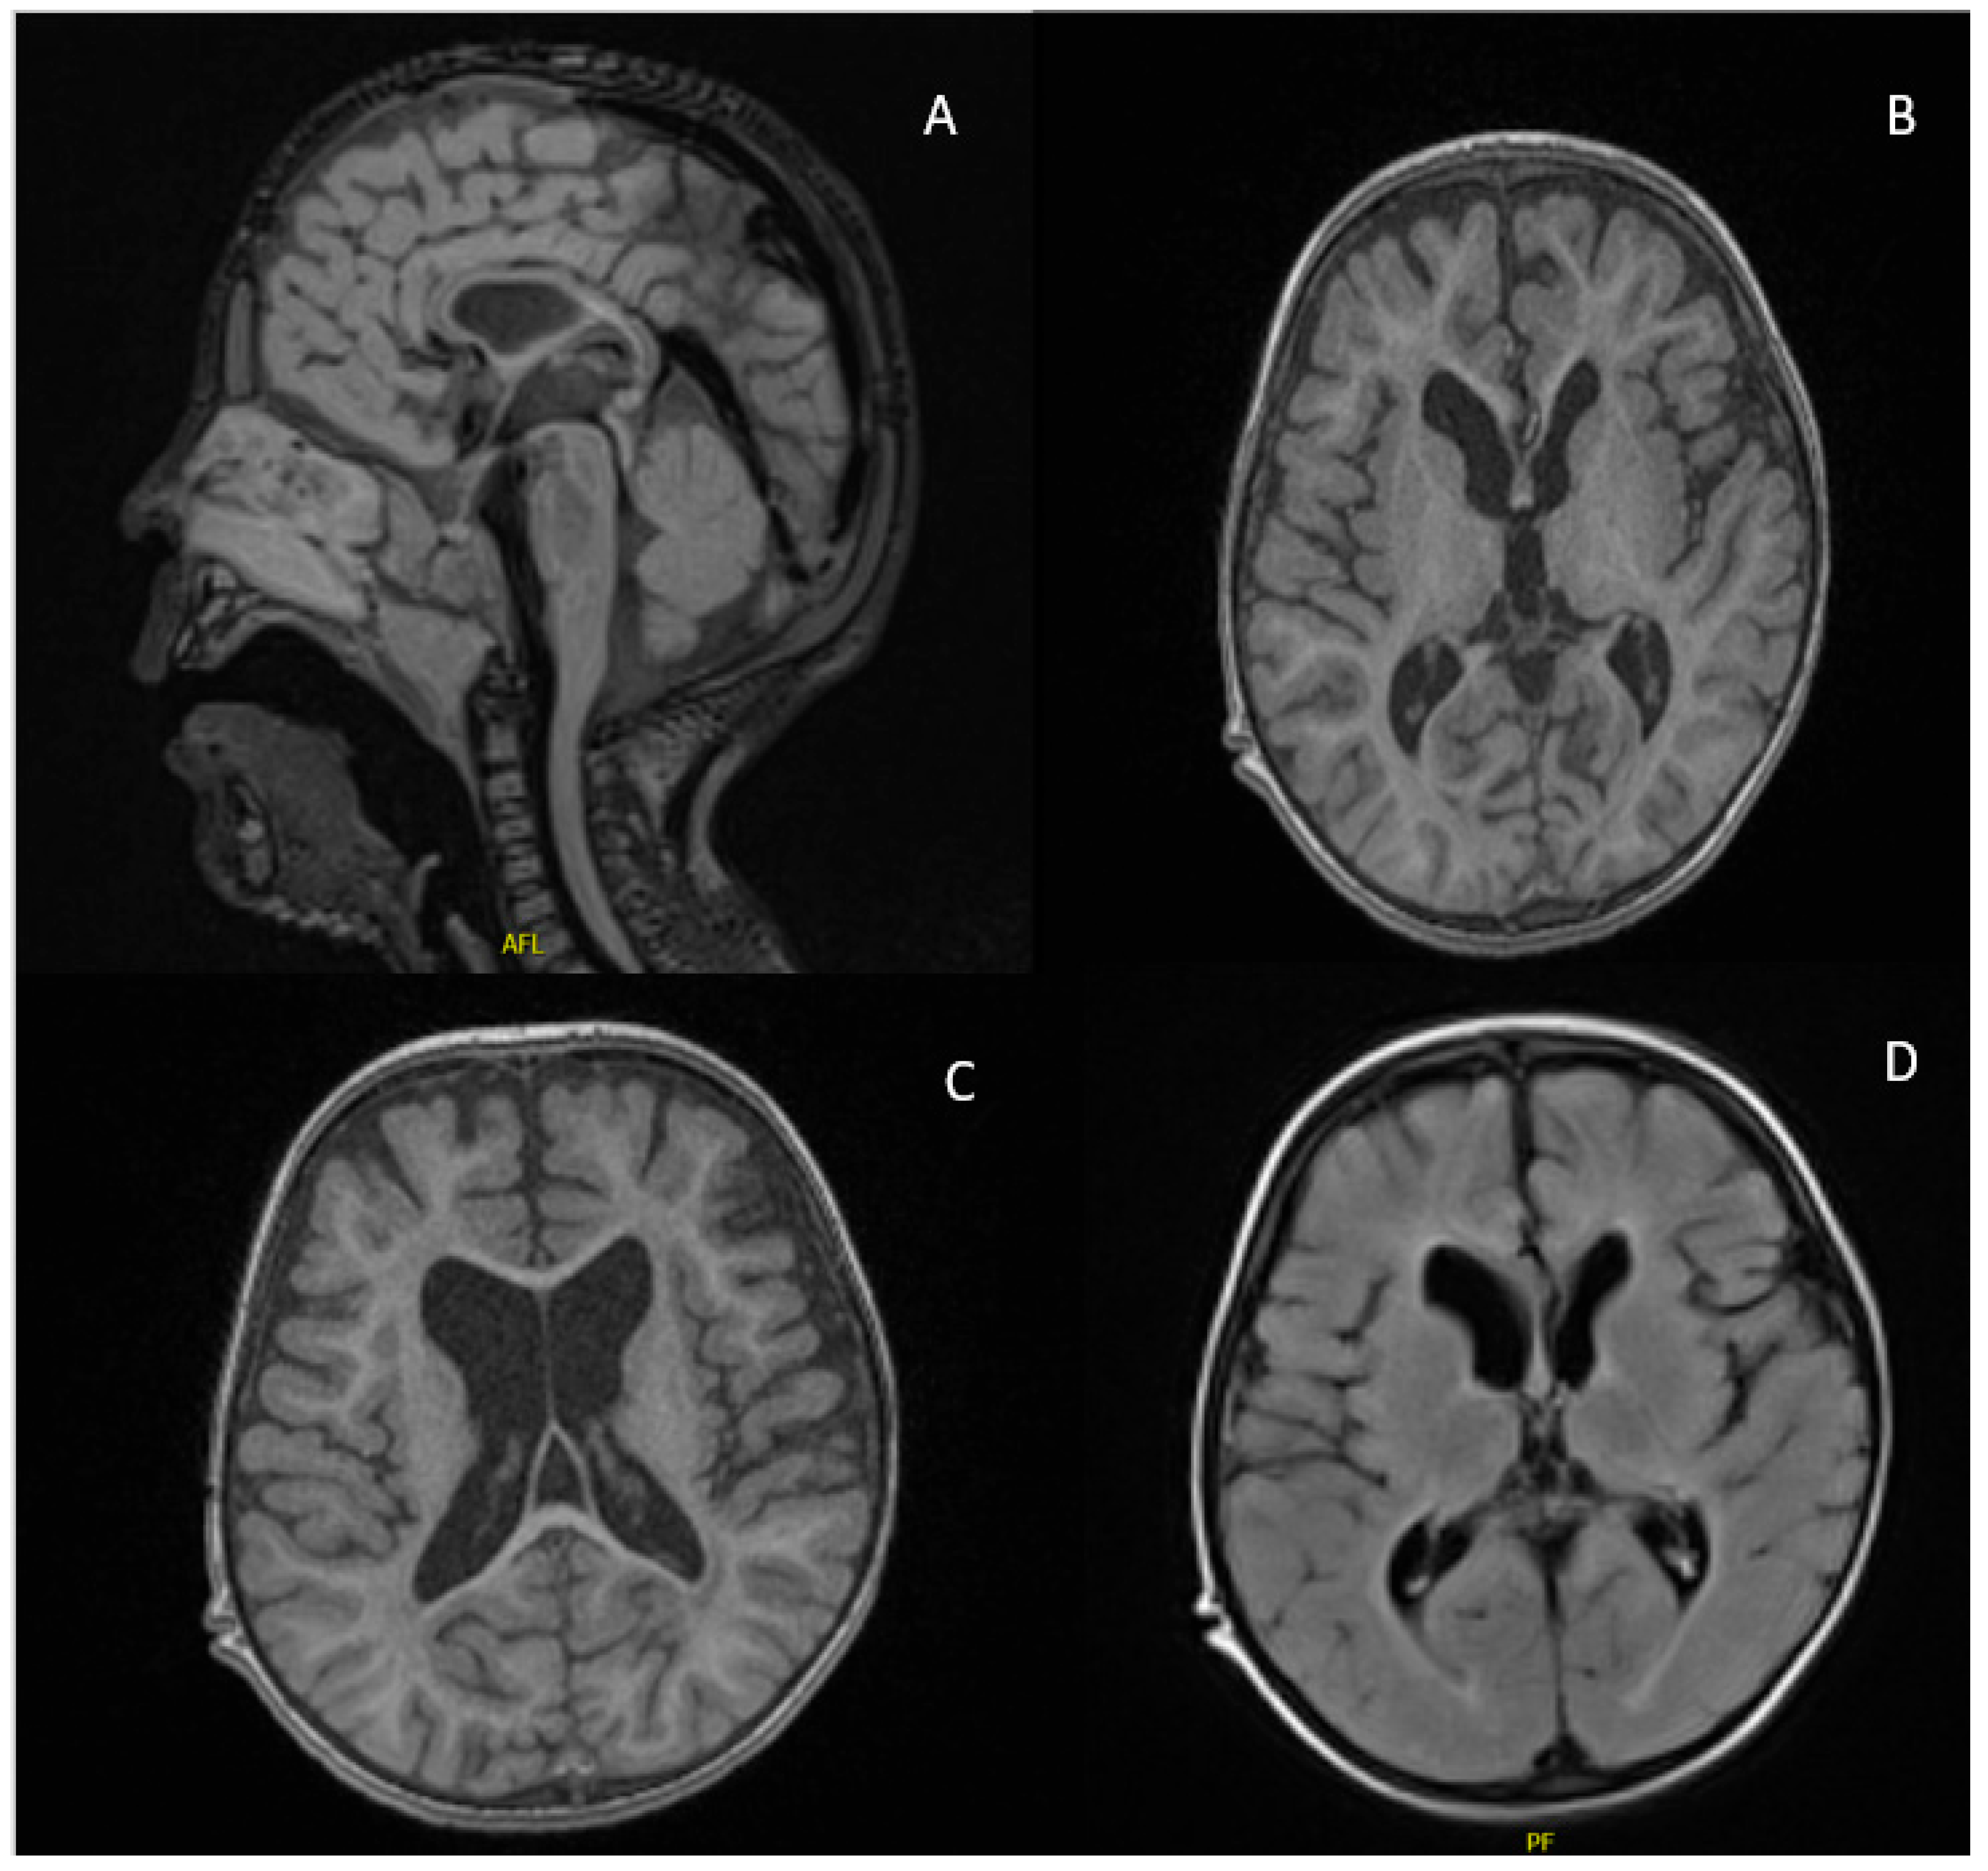

| Neuroimaging | Corpus callosum hypogenesis Hypomyelination Diffuse brain atrophy | Interhemispheric cyst Absent corpus callosum | Semilobar holoprosencephaly Enlargement of the subarachnoid space Corpus callosum agenesis Ventriculomegaly Colpocephaly | ||